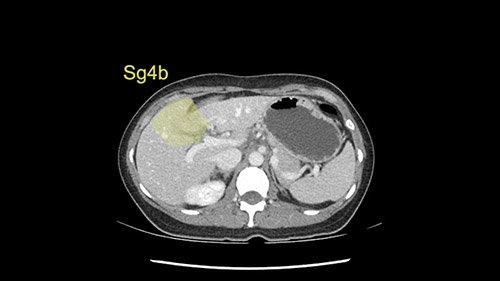

We note that the tumor is pushing on the gallbladder but I think that’s probably external for the most part. I think that’s extrahepatic. I believe that Segment 4b is probably free of tumor. I’d have to say that it's tempting, particularly looking at the coronals, to consider a very limited resection. Where you’d just chip it off the bottom of Segment 3 and do a limited Segment 3 resection. I’d be concerned about the oncologic margins. I believe that the best oncologic operation will be to take the left portal vein to get this. Certainly, she’s got plenty of liver and she’d be able to sacrifice Segments 2-3 of the left lobe of the liver. It’s not necessary to take too much of thus of Segment 4a. But once one takes the portal vein, that will be compromised. So I would do a left hemihepatectomy on this woman.

Tumor proximity to Sg4b

The tumor is so close to the falciform ligament, I had a question mark about the Segment 4b relation between segment 4b and segment 3. In a normal resection of segment 2 and 3, we would be keeping on the left side of the falciform ligament and start getting segment 3 and 2 portal pedicles but in here its getting so close. So oncologically, 4b should be checked during the OR.

What kind of procedure can we plan for this patient? It obviously has to be a left hemihepatectomy because most of the lesion is actually in Sg4. Can we do something which is less than a hemihepatectomy and just do only a segmental resection? The answer to that is that this vascular supply, if you are trying to ligate only the portal venous pedicle to the Segment 4, it is very close to the tumor and you will end up not having not a great margin as far as tumor resection is concerned so I would recommend a left hemihepatectomy and not just a partial or segmental resection. You can also see that it is crossing the falciform line and going on to Segment 2 and 3 so trying to do anything less than a left hemihepatectomy may not give the right kind of margins which we need for this tumor. Fortunately for us, the contours of the liver, which are very important to see in a Hepatitis B patient, there are no cirrhosis which I can see. The normal liver functions indicate that it's a well compensated Hepatitis B.

The other thing I would do in this case is to certainly to assess the coronal phase as we can see in the coronal phase, this tumor looks like it's growing from Segment 3, and again I don’t think there’s involvement of the right side of the liver or even on Segment 4.